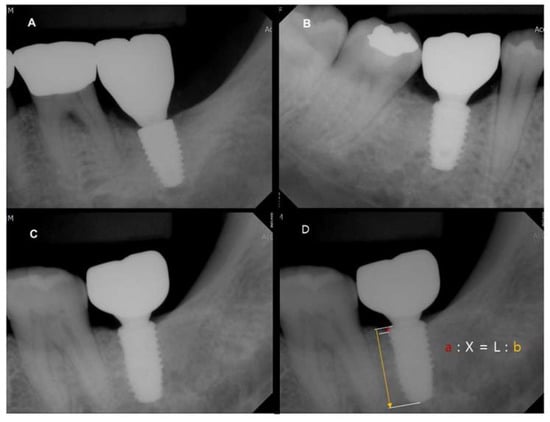

2.4.5. Measurement of Marginal Bone Loss

2.4.6. Recall Visit Procedures and Implant Evaluation